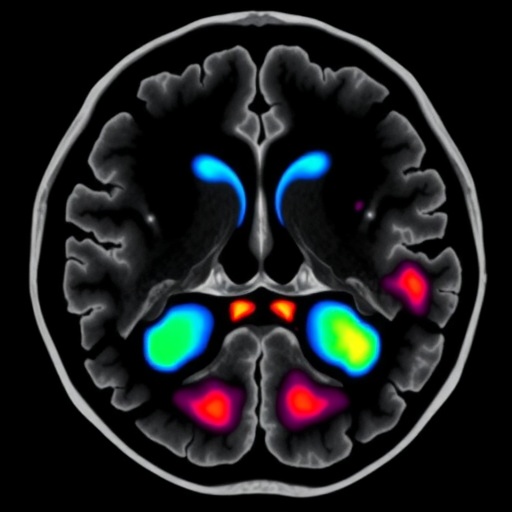

The study, published in BMC Cancer, embarks on this frontier by dissecting the spectrum of soft tissue involvement with unprecedented specificity. Patients diagnosed between 2014 and 2019 underwent rigorous MRI examination, enabling the stratification of muscle invasion severity. The grading system classified STI on a continuum from mild — involving muscles like the tensor veli palatini or levator veli palatini — to moderate, marked by prevertebral muscle involvement, culminating in severe infiltration signified by medial or lateral pterygoid muscle or infratemporal fossa invasion. Complementing this, skull base invasion was grouped based on extent as limited or extensive.

From a radiological perspective, this study underscores magnetic resonance imaging’s evolving role, transitioning from a mere diagnostic tool to a prognostic linchpin. The muscle-specific approach demands meticulous imaging protocol optimization and radiologist expertise to discern subtle variations in muscle infiltration, underscoring the convergence of technological advances and clinical acumen.